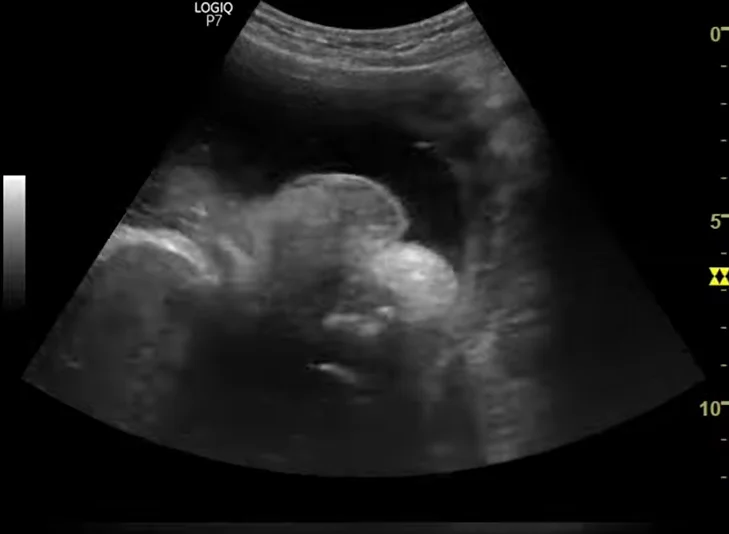

Ứ dịch âm đạo thai nhi (Hydrocolpos) / Ứ dịch âm đạo - tử cung thai nhi (Hydrometrocolpos)

24/05/2026